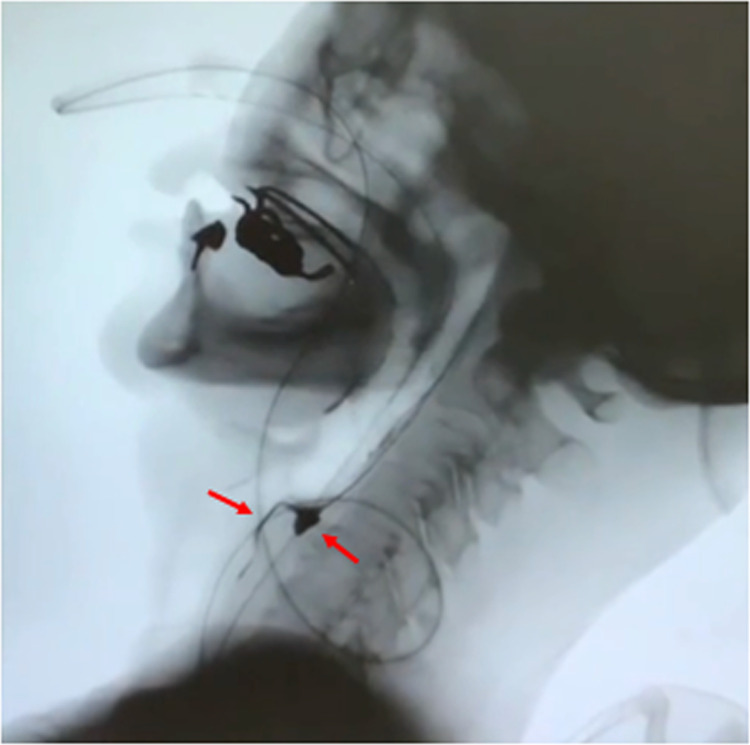

Case: A 76-year-old woman presented with a 4-month history of acute progressive limb muscle weakness and dysphagia. Blood examination revealed significantly elevated creatine kinase (CK) (3472 U/L) and SRP antibody positivity. The patient was near-bedridden and required alternative nutrition. She was treated with oral prednisolone and intravenous immunoglobulin. Rehabilitation therapy was initiated after confirming the decline in CK levels. She started with exercises on the bed and exercise load was gradually increased. Videofluoroscopic swallowing study showed severely weakened pharyngeal contractions and aspiration. Her symptoms improved slowly. She started transferring to a wheelchair after 2 months, gait training using parallel bars after 4 months, and was administered a paste diet once a day after 5 months. Rituximab was administered as additional treatment. Thereafter, the patient started gait training with a walker. The oral paste diet was increased to three times per day after 7 months, and a regular diet was adopted after 9 months. After 11 months, she was discharged home after achieving modified near independence in all activities of daily living.